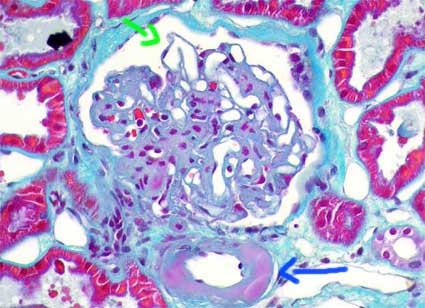

En vasos suele haber lesiones notorias; el cambio más característico es el engrosamiento hialino intimal de arteriolas, a veces nodular (Figuras 8 y 9). Si es muy prominente debe alertarnos sobre la posibilidad de ND sobre todo en jóvenes. Las lesiones arteriolares pueden comprometer cualquier arteriola; si evidenciamos en un glomérulo determinado hialinosis en la arteriola aferente y en la eferente es virtualmente patognomónico de ND. En arterias hay fibrosis intimal (arterioesclerosis), pero no se diferencia de la que se produce en otras enfermedades.

Figura 9. En esta imagen podemos ver una hialinosis arteriolar prominente, con formación de nódulos que remplazan la media de la arteriola glomerular (flecha azul). El penacho muestra ensanchamiento de la matriz mesangial y un microaneurisma capilar en el que parece haberse perdido parte del mesangio que lo sostenía: mesangiolisis (flecha verde). (Tricrómico de Masson, X400).